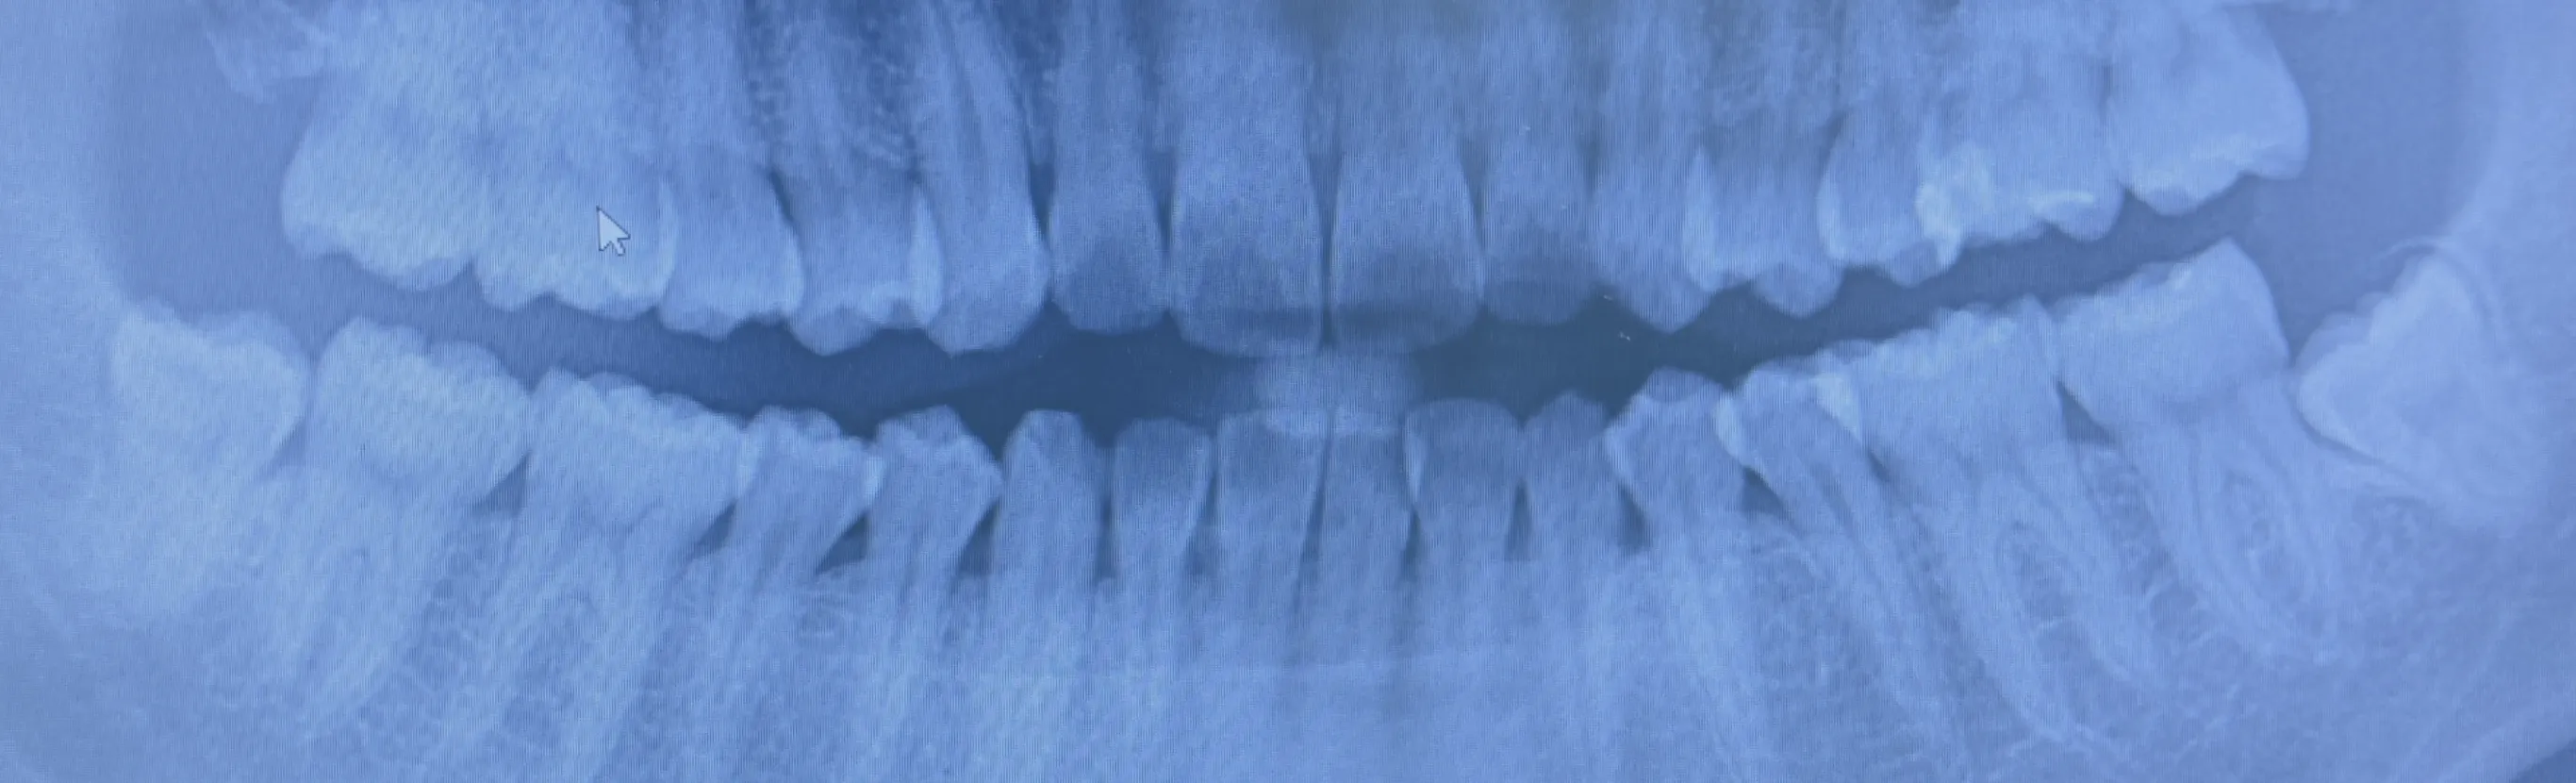

CTスキャンを使用して

正確に診断することで

痛みも少なく安全な治療が出来ます -

親知らずの抜歯は、上の親知らずと下の親知らずで異なります。上の親知らずは、通常すぐに抜歯できます。しかし、下の親知らずは、位置や角度によっては抜歯が難しい場合があります。抜歯が必要かどうかは、レントゲンやお口の状態を診て判断します。